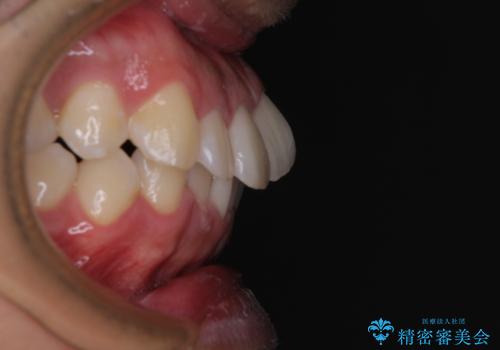

前方に捻れた前歯を治したい インビザライン矯正治療

- 前歯のデコボコを治したいとのことで来院された患者様です。

上下顎ともに歯列全体の後方移動とIPR(歯と歯の間を削る)によってデコボコが解消するように設計し、インビザラインにより治療を行うこととしました。